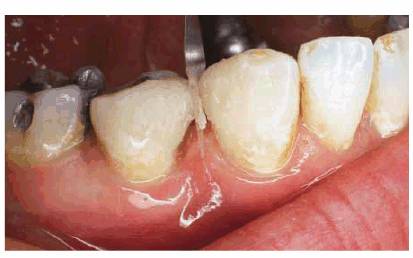

PROBLEM: This 21-year-old male model hesitated to smile because of his

diastemas (see Figures 23-14A, 23-14G, and 23-14I). The patient was also concerned about the appearance

of his inflamed gingiva adjacent to the left central incisor; subsequent

examination showed an overextension of composite bonding. A main requirement of

this patient was immediate esthetic treatment since he was leaving for Italy in

1 week. A second requirement was that no additional tooth be reduced, including

the opposing teeth.

TREATMENT: To maximize longevity and esthetics, porcelain laminates were

chosen as the most conservative treatment. Figure 23-14B shows the previously bonded left central

incisor coated with dentin-disclosing solution to determine how much enamel was

left. The tooth is washed, leaving red dye to indicate dentin areas (see Figure 23-14C). Figure 23-14D shows the left central incisor laminate being bonded

into place. Figure 23-14E shows the occlusal view, indicating just how

much the left central incisor protruded before restoration. Four porcelain

laminates were used to create a symmetric arch with proper spacing (see Figure 23-14F). The improvement by the final result can be

seen by comparing the before and after smiles (see Figures 23-14G and H). Note how the increased tooth size is

well proportioned to the face (see Figure 23-14J). The conventional preparation for a porcelain

laminate veneer when there is no diastema usually extends one-third to midway

into the proximal surface (see Figure 23-14K). However, when closing diastemas, extend the

proximal margins as far to the lingual surface as possible (Figure 23-14L). In addition, extending the preparation to the

lingual surface allows for incorporating more translucent porcelain, which can

keep the teeth from appearing too wide.

RESULT: Frequently, orthodontics is required to reposition teeth

together to avoid the overly contoured appearance of restored teeth. Although

this treatment could have been employed, the patient chose immediate esthetic

correction over lengthy orthodontic treatment.